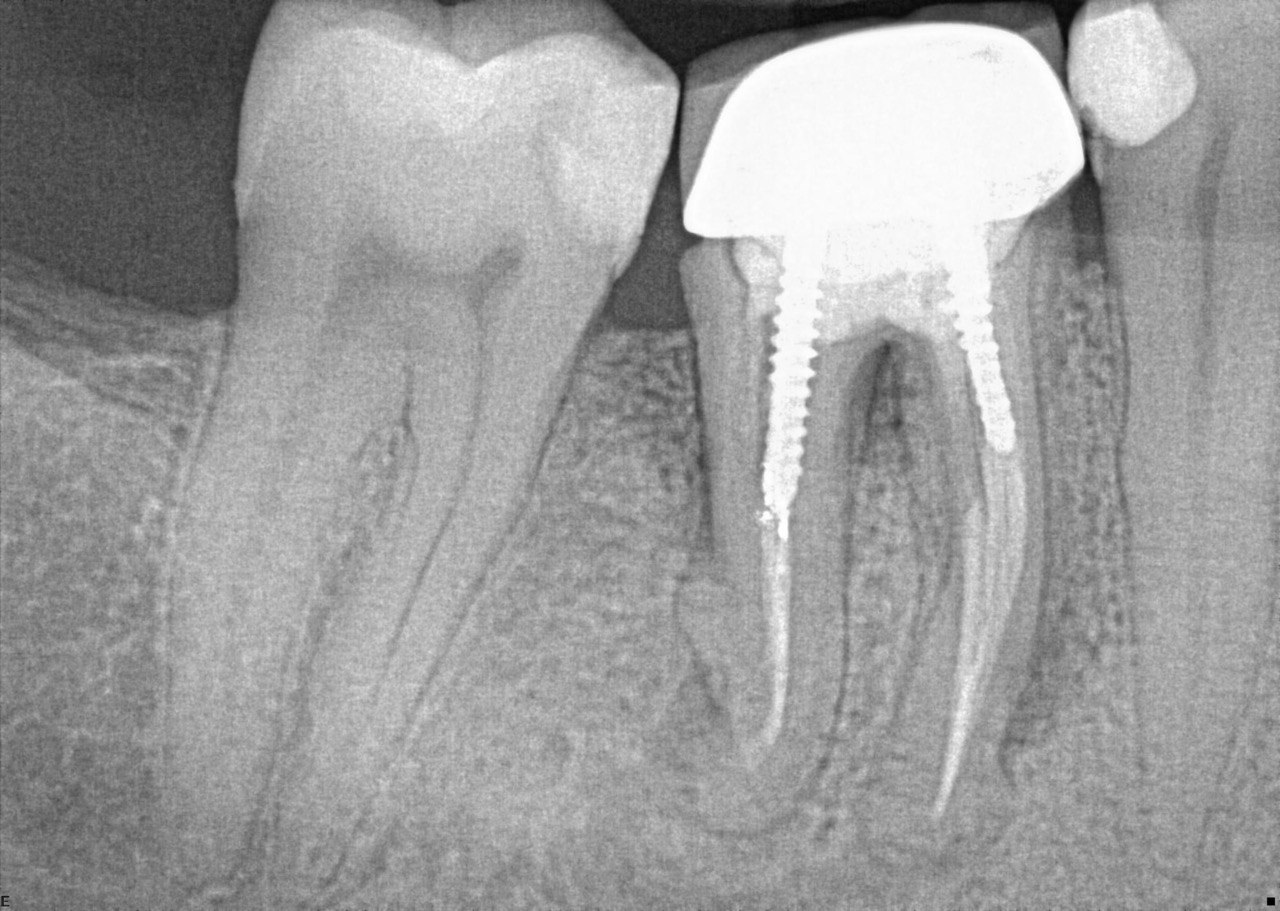

Question 26: What option cannot be selected for mesial tooth surface # 2.8?

Question 27: What options cannot be seen in this X ray?

Question 28: What is the best option that describe distal surface of tooth # 3.5?

Question 29: What options cannot be seen in this X ray?

Question 30: What options can be selected for the tooth # 4.2?

31. What option cannot be selected for the tooth # 3.6?

32. What options cannot be seen in the print of this X ray?

33. What options cannot be seen in the print of this X ray?

34. What option can be selected for tooth # 4.6?

35. What options cannot be selected for the tooth # 1.5?

36. What options cannot be selected for the tooth # 3.7?

37. What options can be selected for tooth # 1.2?

38. What option can be seen in the print of this X ray?

39. What options can be selected for the print of this X ray?

40. What cannot be seen in the print of this X ray?